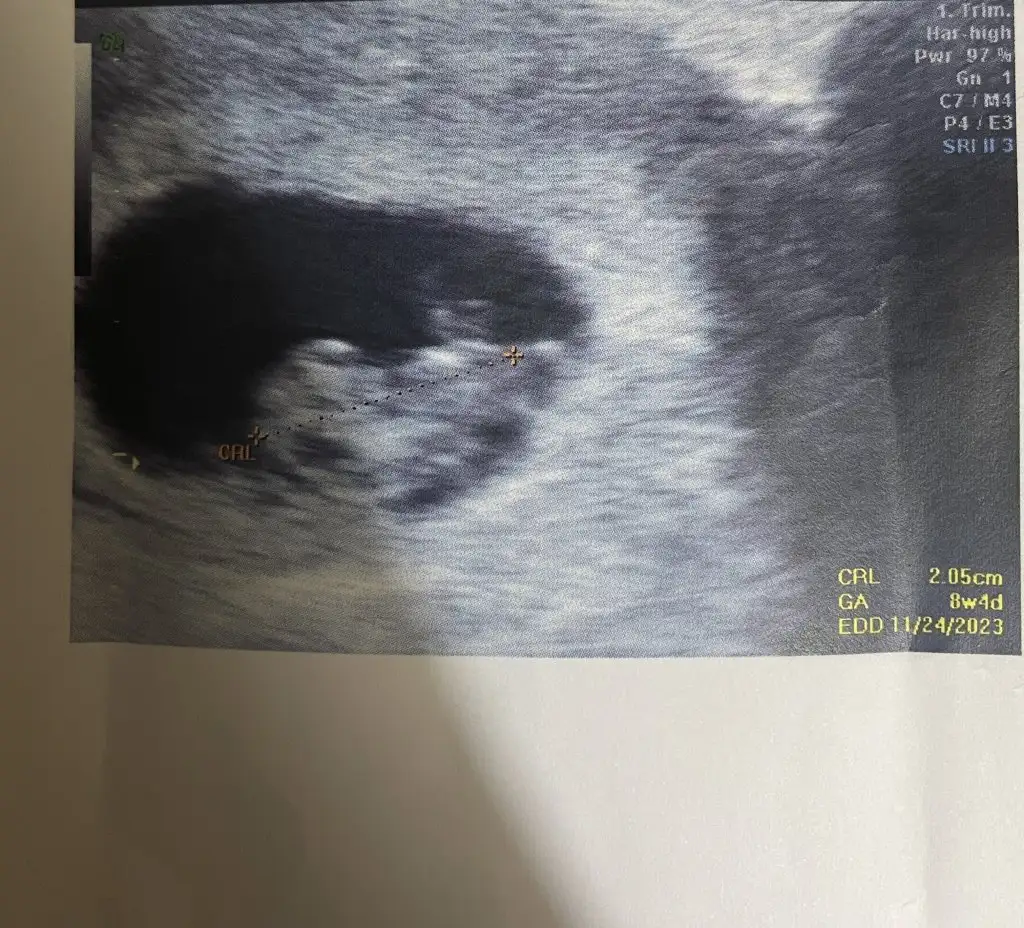

1ciftyesilgozz merhaba kizlar 8 haftalik olduk dun doktora gittik iki oglumdan sonra fikirlerinizi alayim varmi bizede bir tahmin

Eklentiler

• ED29E629-549D-4E18-9554-8B8E59BB173E.webp

16 KB · Görüntüleme: 70

• 2EB25C88-F3C3-4BF4-A081-754B702961A4.webp

94,6 KB · Görüntüleme: 56

• 76529EE5-2145-4C63-8B1D-C3103B91523A.webp

106,6 KB · Görüntüleme: 56